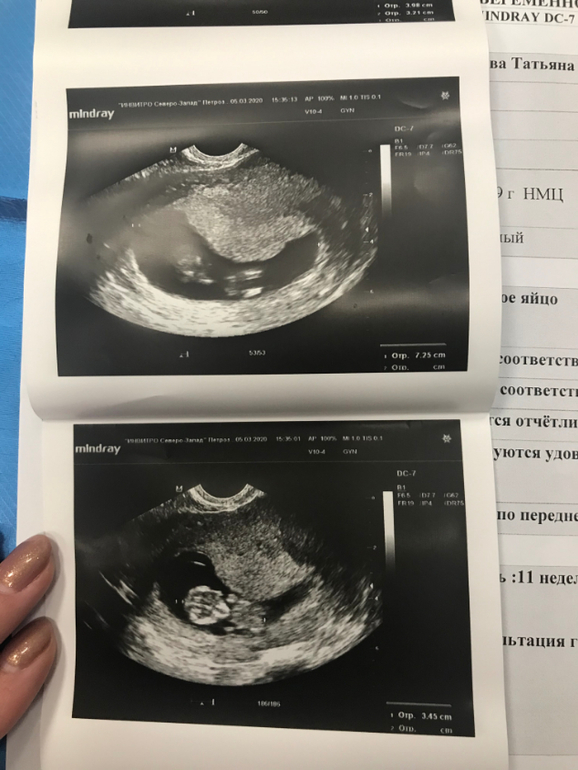

Не всё гладко. к сожалению. Появилась миома, но Г сказала ничего страшного, будем наблюдать. И бесконечный гипертонус, который видимо приводит плодное яйцо в жуткое состояние (на картинке). Я смотрю на фото узи других и вижу, какие у них красивые овальные и круглые домики, а у меня вечно все через ж... Сначала писали ПЯ неправильной формы, потом деформированное, короче какое-то оно странное. Видела вчера на узи как малышу тесно в таком(( Сказали, что пя все равно тоже растет и должно быть всё нормально.

А это в 11

А это в 11